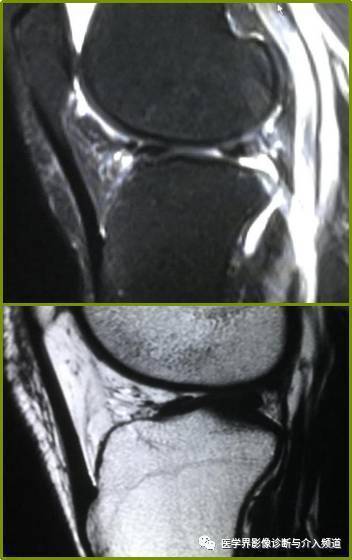

半月板后移征:矢状面上,外侧半月板后 角相对于胫骨外侧平台后移,考虑

横韧带连接内外侧半月板前角,呈现低信号索带样结构 .

膝横韧带3外侧半月板右角偏向内侧,向头侧倾斜,因此在短te时会因魔角

标记:高尔夫球杆形状—外侧层面 标记:不要认为是半月板前角的碎片 矢

半月板桶柄状撕裂矢状面像上半月板体部失去正常的双凹镜形态,前后角